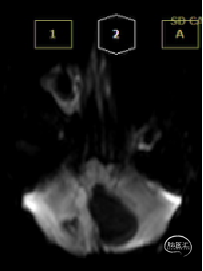

术前MRI

术后MRI